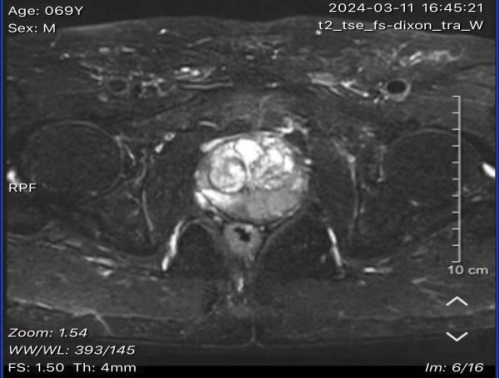

近日,一名69岁男性患者,因反复尿痛半年,夜尿增多约3-4次,遂来建瓯市立医院泌尿外科就诊。查血发现总前列腺特异性抗原>100.00;游离前列腺特异性抗原7.750;fPSA/tPSA 0.00。肛门指诊:前列腺增大、质韧,无明显触痛。磁共振显示:前列腺外周带4-7点方向病变,PI-RADS 5分。经泌尿外科主任医师李永斌、王泳团队讨论与思考,高度怀疑患者为前列腺癌,隧建议请超声影像科黄维拟定超声引导经会阴前列腺活检方案及合作实施活检术,整个过程30多分钟,顺利完成,经病理诊断确诊为:前列腺腺泡腺癌。

(图1为MRI发现前列腺外周带可疑结节;图2为超声双平面探头下前列腺对应区域可疑结节的低频声像)

对于可疑前列腺肿瘤患者一般都会进行磁共振检查,超声图像结合磁共振图像,将两者进行结合,再给出明确的穿刺靶目标,做到个性化诊治,为后续治疗方案提供依据。